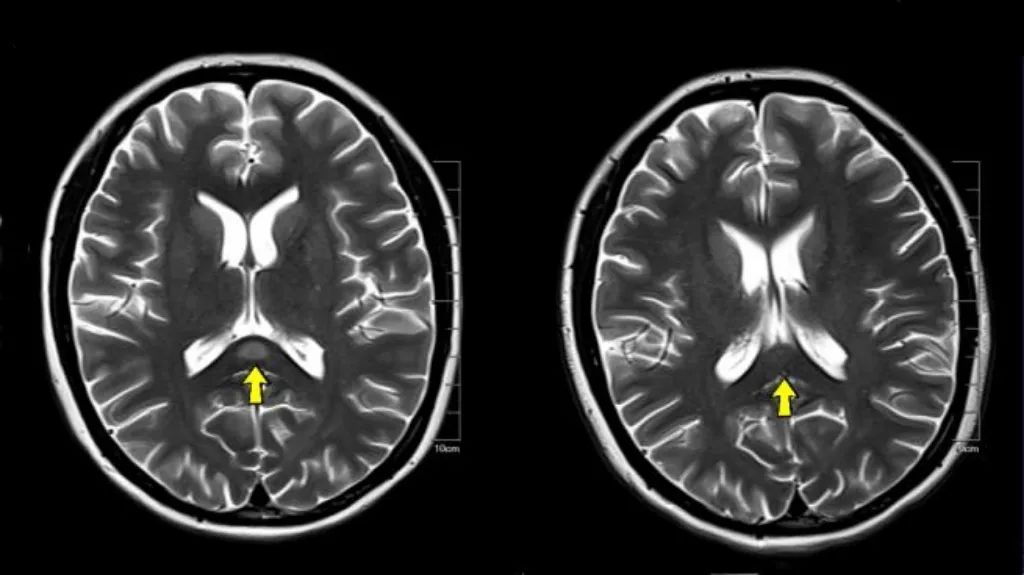

患者治疗前后MRI T2WI影像对比

幸运的是,经过治疗(主要针对可能的诱因和支持治疗),小林的症状迅速改善:不自主运动消失、幻听和味觉异常消失。1周后复查MRI,胼胝体压部的异常信号完全消失,印证了该病“可逆性”的特点。